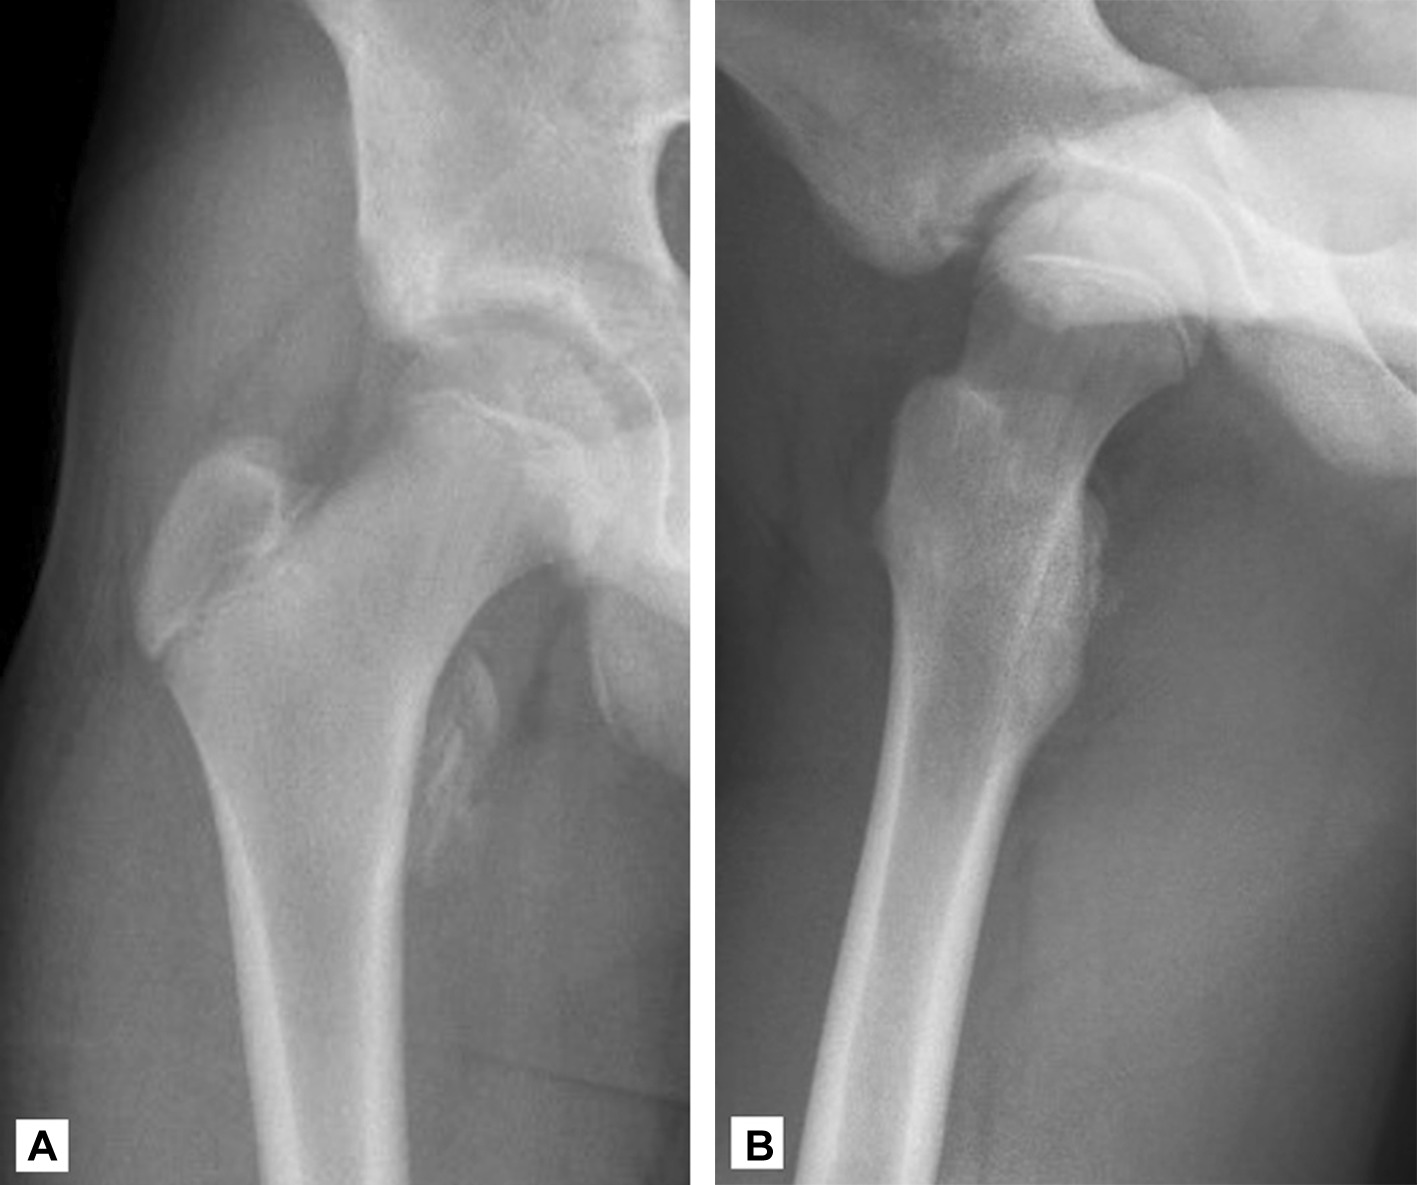

Repérer et palper le grand trochanter, qui est la principale saillie osseuse de l'aspect latéral de la cuisse proximale. Pii avulsion fractures of the lesser trochanter in adolescents are uncommon. It projects from the lower and back part of the base of the neck. Calcaneus via the achilles tendon palpate. Avulsion fractures of the lesser trochanter in adults are almost always due to metastatic bone disease.

Pii avulsion fractures of the lesser trochanter in adolescents are uncommon. Calcaneus via the achilles tendon palpate. Isolated lesser trochanter fractures in adults should be considered pathological until proven otherwise. The lesser trochanter (trochanter minor; Study 39 muscle palpation flashcards from lauren s. Bilateral lesser trochanter avulsion fractures in an adolescent. Its principles and the cervical disc. Afin de faciliter le positionnement de la sonde.

Bilateral lesser trochanter avulsion fractures in an adolescent. Its principles and the cervical disc. Study 39 muscle palpation flashcards from lauren s. In elderly patients, the most common lesions are metastasis, myeloma or lymphoma. Two muscles insert onto the lesser trochanter With the patient supine, palpate the anterior joint line just lateral to the femoral artery pulsation, below the middle third of the. For the surgeon's orientation, in order to determine the level of the osteotomy, perform a palpation of the lesser trochanter and the fossa piriformis. The less common tendinitis and partial tears of the distal biceps tendon present with localized pain and. The lesser trochanter (trochanter minor; Soleal line of tibia, posterior head of fibula i: Upper extremity of right femur viewed from behind and above. Havept flex hip with your palpation soleus: If you wish to palpate on the skin, provide a private room for assessment.

We report three patients with avulsion of the lesser trochanter due to neoplasm.

350 x 234 jpeg 11 кб. The iliopsoas musculotendinous unit can be injured from repetitive, excessive, or unbalanced contraction while. Bilateral lesser trochanter avulsion fractures in an adolescent. The greater trochanter is situated on the proximal and lateral side of the femur , just distal to the hip these bursae and the periosteum of the greater trochanter are innervated by a small branch of the. It is directed lateral and medially and slightly posterior. We report three patients with avulsion of the lesser trochanter due to neoplasm. Isolated lesser trochanter fractures in adults should be considered pathological until proven otherwise. Small trochanter) is a conical eminence, which varies in size in different subjects; If you wish to palpate on the skin, provide a private room for assessment. Superior ramus of pubis to just distal of lesser trochanter. A little understood disorder of the vertebral joint. The greater trochanter is located proximally and laterally on the femur, just distal to the hip joint and the neck of the femur. Lesser trochanter bsis are less common compared with femoral neck bsis.